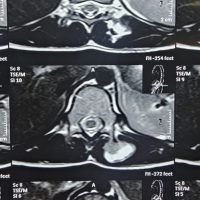

Magnetic resonance imaging (MRI) of the spine demonstrated altered heterogeneous signal intensity involving the marrow and a compression fracture L5, with reduced vertebral height was causing significant spinal canal stenosis and cauda equina compression. These findings were suggestive of a pathological fracture due to MM (Fig. 3).

Figure 3: Magnetic resonant images showing L5 vertebral compression fracture with decreased vertebral height is seen causing significant stenosis of spinal canal and compression of cauda equina (a) Sagital T2 weighted image, (b) Axial T2 weighted image, (c) Coronal T2 weighted image).